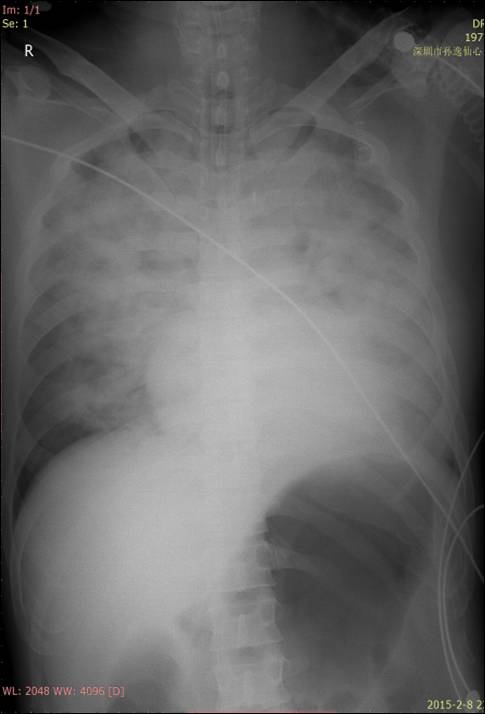

胸片

急性

肺水肿